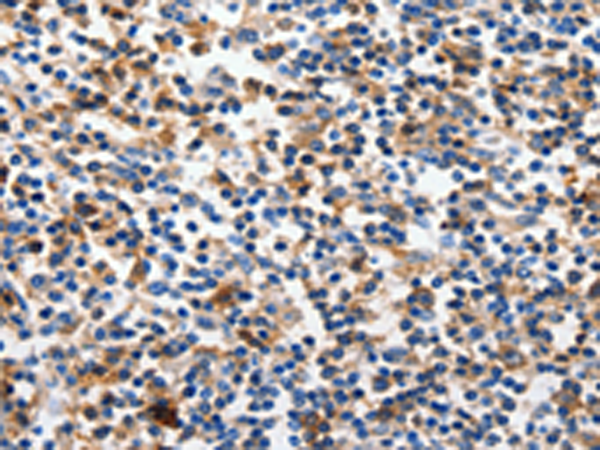

分类: 科研抗体货号: P10761别名: KACL; PILAR; UNQ5792应用: IHC反应种属: Human